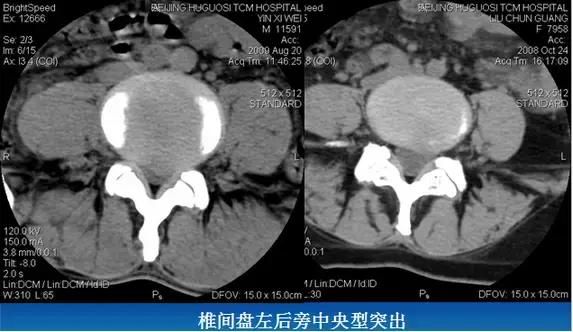

⑵旁中央型:椎间盘影局限性超出椎体边缘,神经根受压。